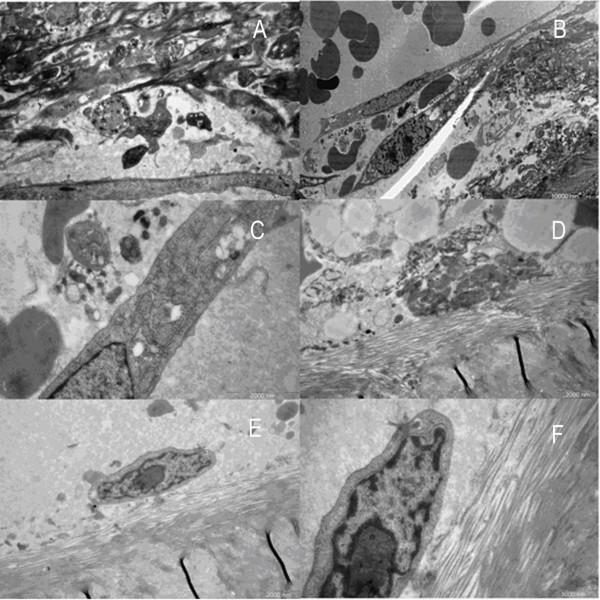

To compare the exact difference in bone tissue structure between osteoporosis and osteoarthritis, we observed the ultrastructure of trabecular bone from the femoral heads using scanning electron microscopy (SEM) and transmission electron microscopy (TEM). A total of 15 femoral head specimens from postmenopausal women were collected during the procedures of total or hemi hip replacement (OP, n = 8; OA, n = 7). The morphologic structure of the trabecular bone, collagen fibers, resorption lacuna and osteoblasts were observed.

Under SEM, osteoporotic trabeculae appeared to be thinning, tapering, breaking and perforating. A number of resorption lacunae of various shapes were seen on the surface of the trabeculum. The collagen fibers of lacuna were resorbed. On occasion, naked granular bone crystals could be found. In the OA group, the trabecular bone looked thick with integrated structure. Reticular and granular new bone could be found. The trabeculum was covered by well-arranged collagen fibers around the resorption lacuna. In the OP group, under TEM, marginal collagen fibers were observed to be aligned loosely with enlarged spaces. A few inactive osteoblasts and no inflammatory cells were seen. In the OA group, the collagen fibers inside the trabeculum were arranged in a dense manner with many active osteoblasts and inflammatory cells infiltrating the matrix.

在SEM下,骨质疏松的小梁骨显得变薄、变细、断裂和穿孔。在小梁骨表面可见许多各种形状的吸收陷窝。陷窝内的胶原纤维被吸收。偶尔可以发现裸露的颗粒状骨晶体。在OA组,小梁骨看起来厚实,结构完整。可以发现网状和颗粒状的新骨。在吸收陷窝周围,小梁骨被排列良好的胶原纤维覆盖。在OP组,在TEM下,观察到边缘胶原纤维排列松散,间隙增大。可见少数不活跃的成骨细胞,未见炎症细胞。在OA组,小梁骨内的胶原纤维排列密集,有许多活跃的成骨细胞和炎症细胞浸润基质。